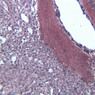

The first site of defense against foreign agents entering the body through the mouth and nose is the ring of tonsils around the posterior oro- and nasopharynx. The tonsil is a mass of confluent lymphoid nodules beneath the pharyngeal epithelium. Examine slide A-41 (retic-H&E [2.5x, 2.5x-labeled] [2.5x, 10x-labeled, 20x, 40x] [2.5xlabeled, 10x, 20x, 40x]). Tonsillar tissue is not separable into cortical and medullary regions, and it does not contain lymphatic vessels. The lymphoid masses, as in the nodules of the stomach and intestine, lie just beneath the epithelium where they can intercept bacteria and viruses that either invade or are phagocytosed by the overlying epithelium. The tonsil is invested by a fibrous tissue and is incompletely subdivided by inward-projecting trabeculae. Blood vessels in the tonsillar substance leave randomly through the fibrous tissue. What features differentiate the tonsil from the ileum?

1 Epithelium Ep H&E a41b lymphoid nodules tonsils 2x labeled.jpgA41, Tonsil, 2.5x

2 Tonsillar Crypt TC H&E a41b lymphoid nodules tonsils 2x labeled.jpgA41, Tonsil, 2.5x

3 Lymphatic Nodule LN H&E a41b lymphoid nodules tonsils 2x labeled.jpgA41, Tonsil, 2.5x

4 Stratified Squamous Epithelium SSE H&E a41 tonsils 10x labeled.jpgA41, Tonsil, 10x

5 Trabecula (none) H&E a41b tonsils 2x labeled.jpgA41, Tonsil, 2.5x